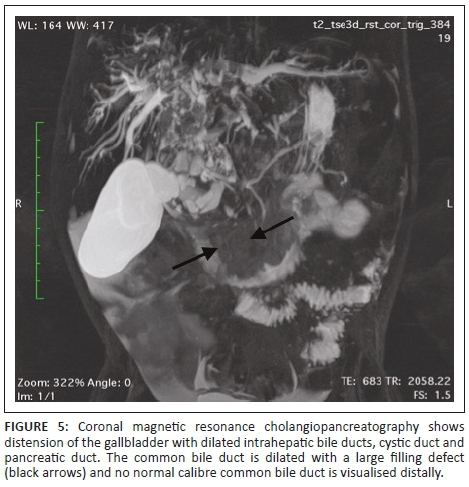

Magnetic resonance imaging (MRI) of the abdomen and magnetic resonance cholangiopancreatography (MRCP) with contrast were of added value in better delineating the origin and extent of the mass already suspected of being bile duct in origin on CT. The lesion filled the dilated CBD (Figure 3) and demonstrated asymmetric mural thickening of the CBD (Figure 4). There was associated dilation of the gallbladder and a small calculus was noted within the dilated cystic duct (Figure 4). The contrast-enhanced MRI demonstrated heterogeneous enhancement within the solid components of this mass. Magnetic resonance cholangiopancreatography illustrated a dilated CBD with a large filling defect as well the previously noted findings of dilated intrahepatic bile ducts and pancreatic duct (Figure 5).